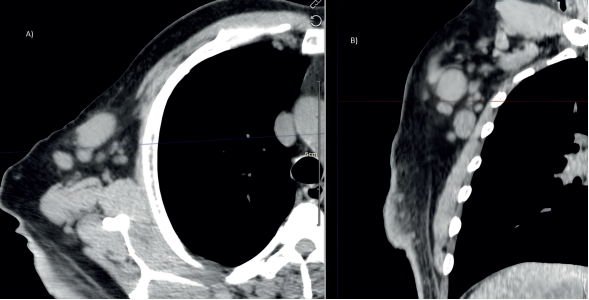

El paciente fue evaluado por el servicio de dermatología, que sugirió inicialmente una dermatosis localizada en la región escapular derecha, posiblemente un dermatofibrosarcoma. Se realizó una biopsia, cuyo resultado indicó un carcinoma con diferenciación anexial, sugestivo de pilomatrixcarcinoma. Ante estos hallazgos, se recomendó valoración por oncología y se optó por una resección amplia de la lesión, seguida de reconstrucción en colaboración con el servicio de cirugía plástica (figura 4). Adicionalmente, se iniciaron ciclos de quimioterapia con cisplatino y 5-fluorouracilo (5-FU).

Imagen: Calderón Valderrama, et al.

Figura 4 Fotografía de la región dorsal con cambios postquirúrgicos y postquimioterapia. Se observa una herida de gran tamaño con algunas áreas ulceradas.